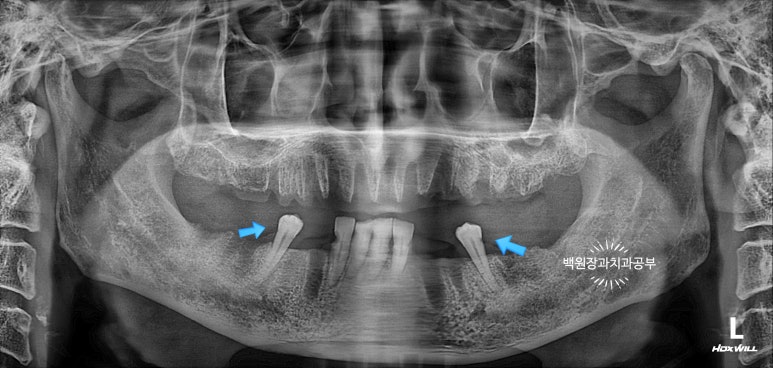

맨 처음 파노라마와 같은 치과 파노라마 사진인데요, 파란색 화살표로 표시해 둔 두 개의 치아가 근심측으로 경사져 있어서 (앞으로 누워 있어서) 이상적인 형태의 보철물을 만드는데 제약을 만들고 있었어요.

그리고 앞니들은 인접면 충치가 심하였습니다. 살려볼 수는 있지만, 비용적으로 심미적으로 더 불리할 것으로 예상되었습니다.